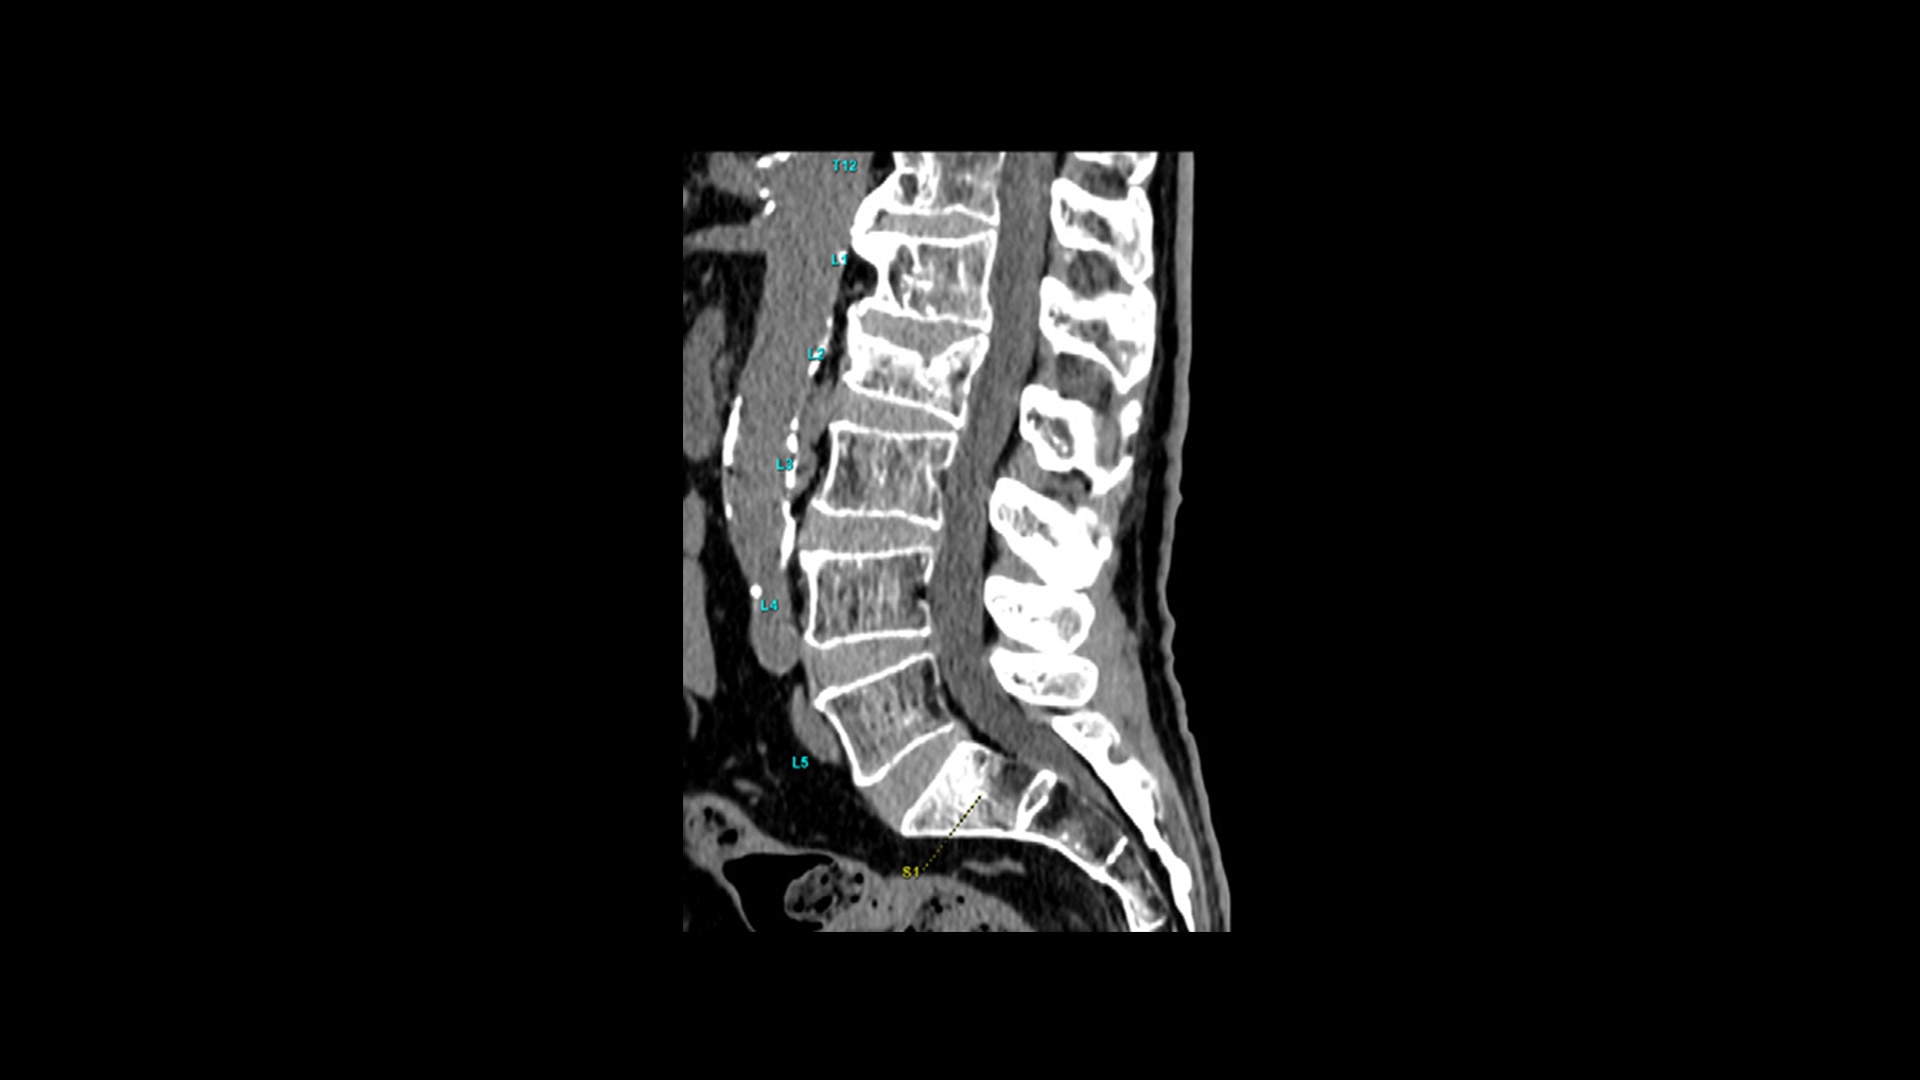

TrueFidelity™ DL is our state-of-the-art image reconstruction technology that uses a DNN to generate high-definition, low-noise CT images. It produces images with exceptional sharpness, low-contrast image quality performance and your preferred noise texture, at the same dose.¹

feature-hero-truefidelity-dl-desktop